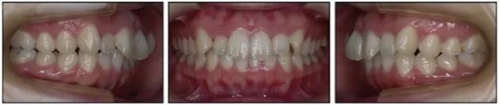

1.基本信息:女性,24歲2月,主訴上前牙及上唇不美觀(圖1)。因美觀問題不愿使用上頜固定矯治器。

2.檢查:凸面型、骨性II類,安氏II類1分類錯合畸形。面型正中對稱,下面高略高,頦部后縮,唇肌略緊張。無顳下頜關(guān)節(jié)癥狀,下頜運(yùn)動正常,無偏斜。上下頜中線與面中線相一致,所有恒牙存在,口腔衛(wèi)生可,牙周情況可。患者健康,無系統(tǒng)性疾病,無牙科創(chuàng)傷史及不良習(xí)慣,懷疑遺傳因素導(dǎo)致錯合畸形。

3.測量分析:治療前記錄提示該患者左右磨牙與尖牙為安氏II類關(guān)系,上頜牙弓重度擁擠,下頜牙弓輕度擁擠,深Spee曲線。6.3mm深覆蓋,80%深覆合。牙齒無齲,無第三磨牙。